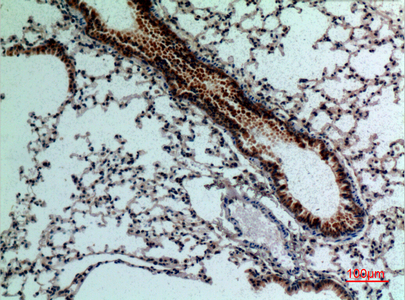

- Scientific DescriptionRabbit polyclonal antibody to FGF18.